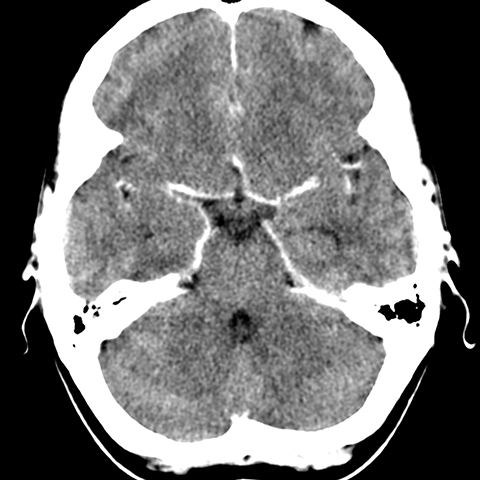

Cerebral Hemispheres, CT (normal) [4 of 6]